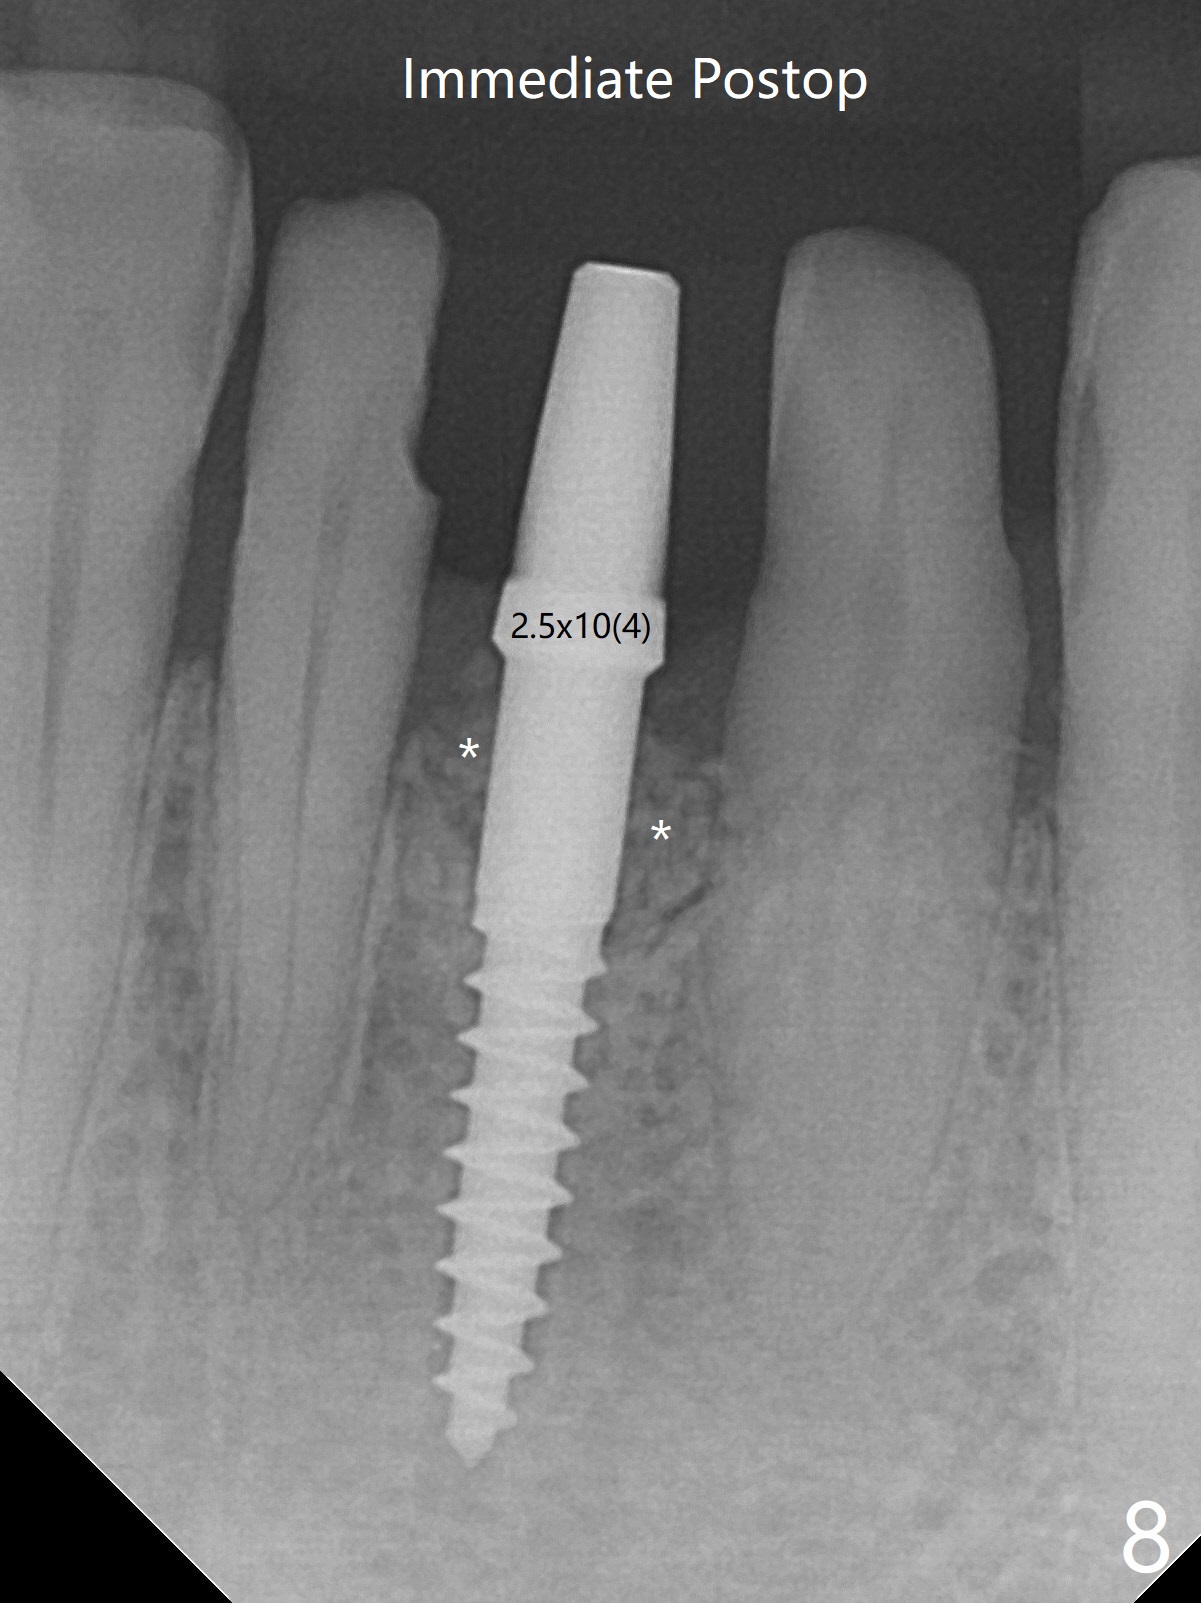

经过深洗以及改善口腔卫生,术前下前牙区牙龈基本没有红肿,但是缺牙处牙龈凹陷(图一,二:箭头),这个现象代表什么?如何影响手术进路?其实后者部分是因为牙龈与下面骨质(骨嵴)粘连(图三:*)产生的,分离粘骨膜瓣时不小心撕裂颊侧牙龈(图三(骨膜分离器下面:#),造成后来缝合困难,需要多用一个胎盘膜)。如果术前仔细分析CT 3D图像(图四,五)可以发现严重颊侧骨壁凹陷(图三:^)以及骨嵴(图四:*),事先抽血制备PRF膜和粘性骨粉,植骨效果好些(图六)。术中发现缺损,再抽血会拖延手术。最后将就用血调袢骨粉,使用胶原膜和胎盘膜覆盖(图七,八)。颊侧裂口术后十天愈合了(图九,十)。术后一个月颊侧牙龈凹陷,牙桥边缘(图十一:箭头)粗糙,临时牙桥取出,调整边缘,有利于局部卫生(图十二)。术后两个月桥边缘光滑(图十三:箭头),局部卫生和牙龈凹陷有所改善。病人将一个半月后回来取模。Return to Protect Graft 前磨牙即种 101 Xin Wei, DDS, PhD, MS 1st edition 04/30/2021, last revision 07/03/2021